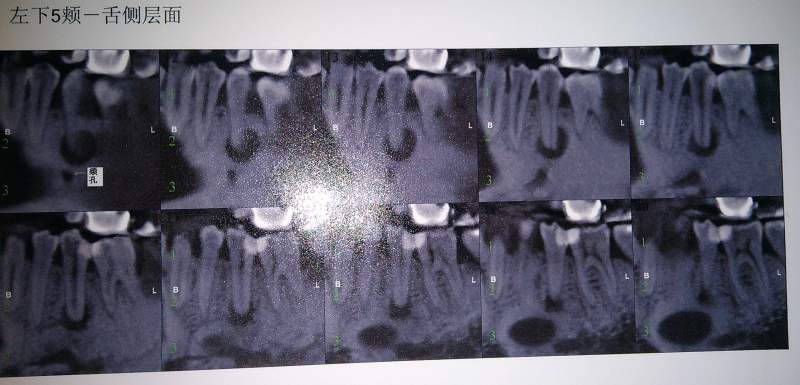

Çë½Ì¸÷λ´óÉñ£¬¹ØÓÚ¸ù¼âÄÒÖ׸ù¹ÜÖÎÁƺóµÄÑÀƬ ÒÑÓÐ2È˲ÎÓë